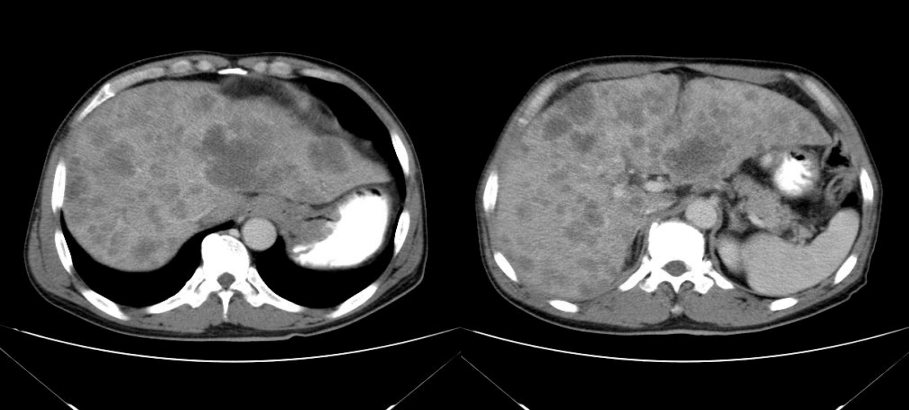

肝脏丨转移瘤影像表现

图片尺寸1080x607